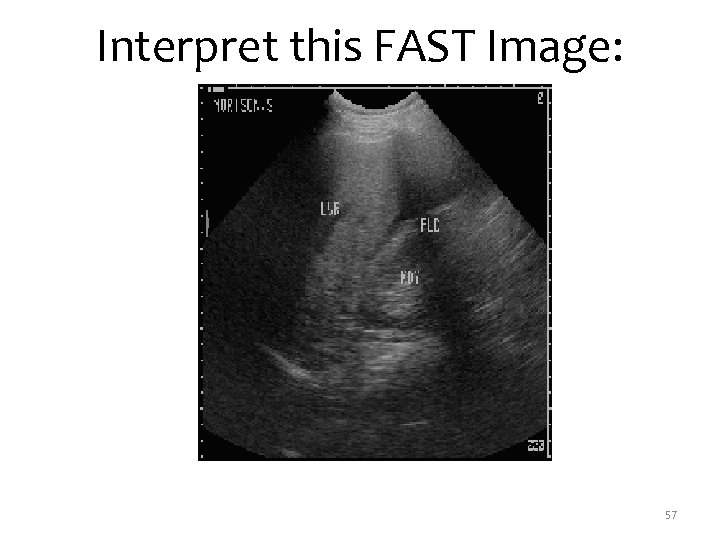

Interpret this FAST Image: 57